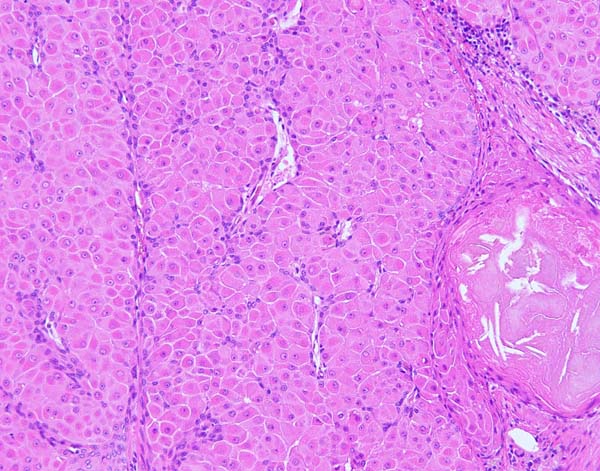

ワンちゃんが乳腺にできた複数のシコリを気にされて来院されました。bilateral mastectomyで対応しました。摘出後の病理組織検査の結果は、「R3-4間腫瘤:乳腺癌(複合型)」でそれ以外は「良性乳腺混合腫瘍」でした。無事元気に退院し、その後再発もなく経過は良好です。よかったね。